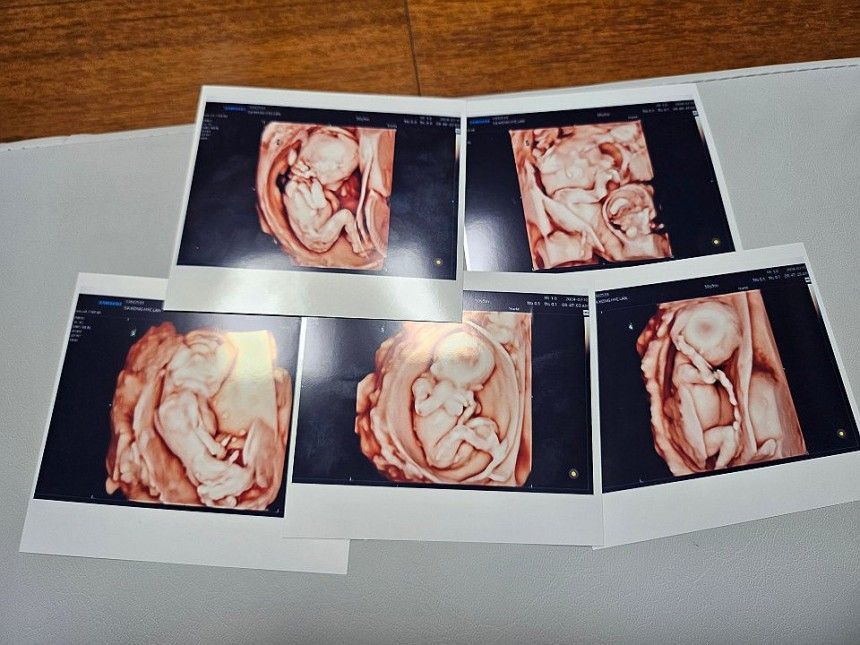

서울성모병원은 지난 9월 20일 낮 남자아이 3명과 여자아이 2명의 '오둥이'가 건강하게 태어났다고 밝혔다. 사진은 오둥이의 초음파 사진. 서울성모병원